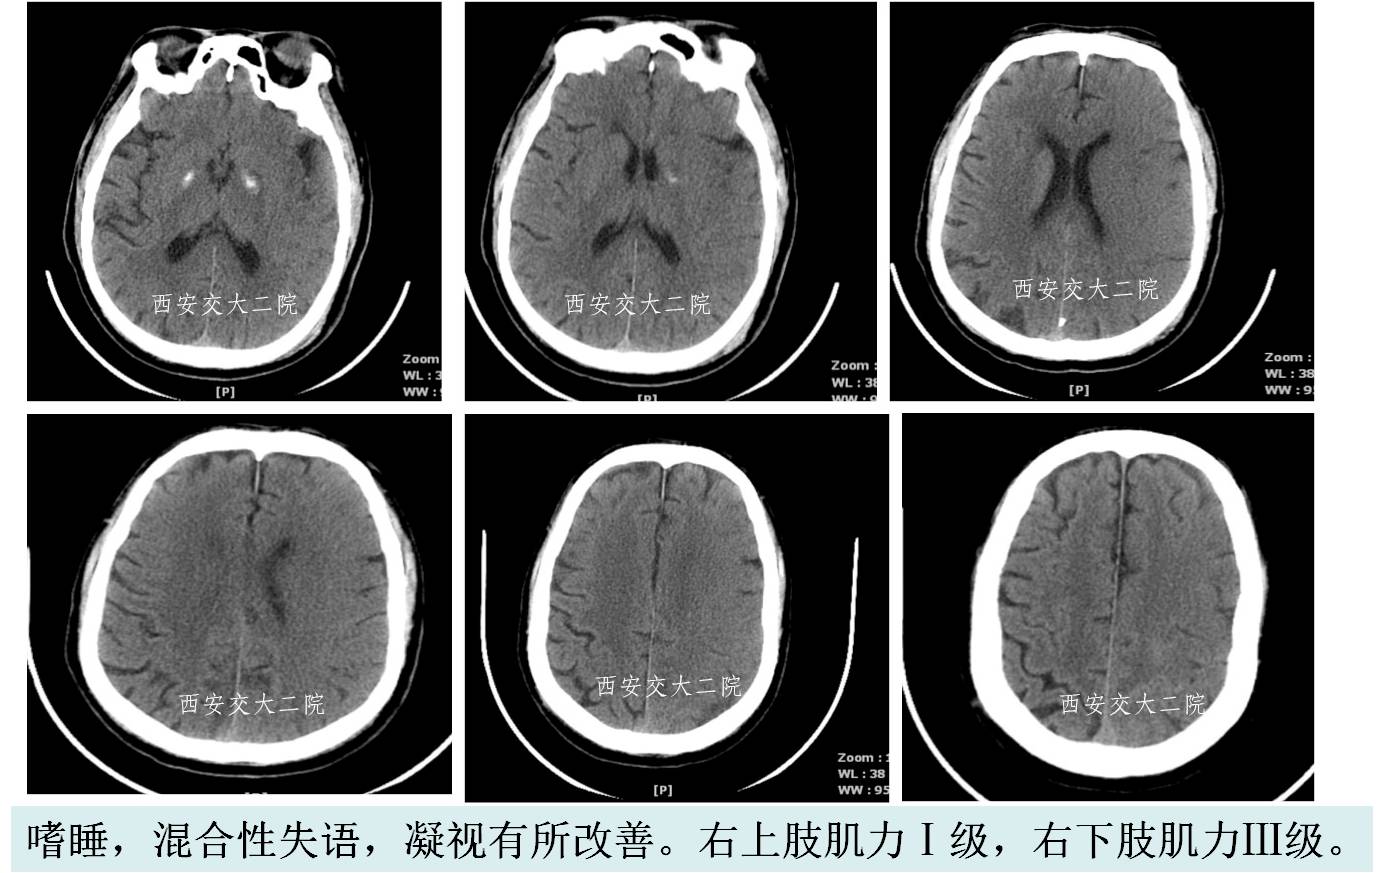

术后24h脑CT及临表

术后4天脑CT及临表

术后2周脑CT及临表